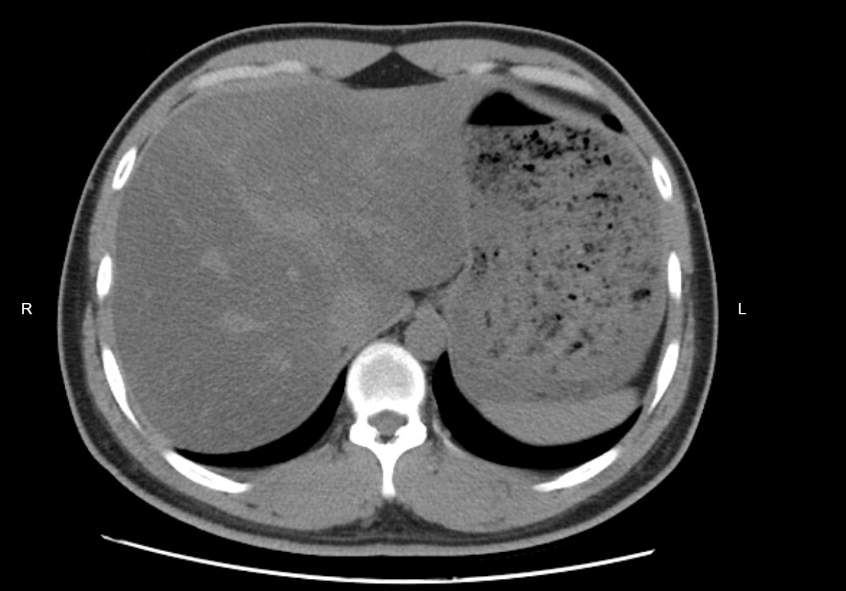

令她始料未及的是,B超检查提示,脂肪肝为中重度。吃素半年,脂肪肝的程度反而加重了。

杨乃彬提醒,仅从体型和体重来判断是否得脂肪肝并不科学。医生会综合肝功能等生化检查、肝脏B超等影像学检查来做综合判断。